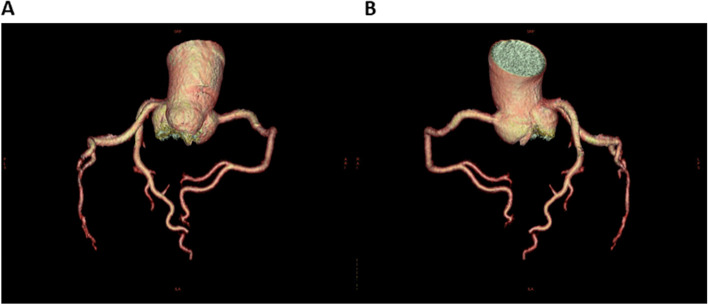

Based on her clinical course and imaging findings, she was diagnosed with reversible cerebral vasoconstriction syndrome (RCVS) with cardiac involvement. We administered 5 mg of the calcium channel blocker amlodipine besylate, 25 mg of nitroglycerin, and 500 mg of the antiepileptic drug levetiracetam. The hyperintense regions on FLAIR images completely disappeared 23 days after onset of first headache. She showed no exacerbation of heart failure, and the ECG (Fig. 3B) and UCG (Fig. 4B) findings were found to be normal eight days after onset of first headache. To avoid the risk of vascular spasm by iodinated contrast medium, we did not perform cardiac catheterization or coronary computed tomography (CT)-angiography until her RCVS was fully controlled. Since no recurrence of symptoms was observed after the treatment, we performed coronary CT-angiography seven months after the onset, which showed no significant vasoconstriction in any coronary artery (Fig. 5A, B).

Fig. 5.

Computed tomography (CT) angiography at 7 months after onset of first headache. Coronary computed tomography (CT) angiography 7 months after onset showed no significant vasoconstriction in any coronary artery. Part (A) shows right anterior oblique (RAO) artery images, and part (B) shows left anterior oblique (LAO) artery images